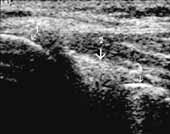

Перевод датчика на область ниже надколенника дает возможность определить поверхностно

расположенную собственную связку надколенника, ее структуру, поднадколенниковое

жировое тело, поднадколенниковую синовиальную складку, глубже которой расположена

передняя крестовидная связка (Рис. 4). Наличие гиперэхогенных включений

передней крестовидной связки свидетельствует о ее кальцинозе (лигаментозе) (Рис.

Рис. 4. Коленный сустав в норме. Поднадколенниковая область,

сагиттальная проекция; 1(+) — собственная связка надколенника, 2

— поднадколенниковое жировое тело, 3 — поднадколенниковая синовиальнакя

складка, 4(+) — передняя крестовидная связка.